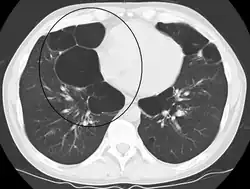

Advanced centrilobular emphysema showing total lobule involvement on the left side

Centrilobular emphysema, also called centriacinar emphysema, affects the centre of a pulmonary lobule (centrilobular) in the lung, the area around the terminal bronchiole and the first respiratory bronchiole, and can be seen on imaging as an area around the tip of the visible pulmonary artery. Centrilobular emphysema is the most common type usually associated with smoking, and with chronic bronchitis.[17] The disease progresses from the centrilobular portion, leaving the lung parenchyma in the surrounding (perilobular) region preserved.[23] Usually the upper lobes of the lungs are affected.[17]